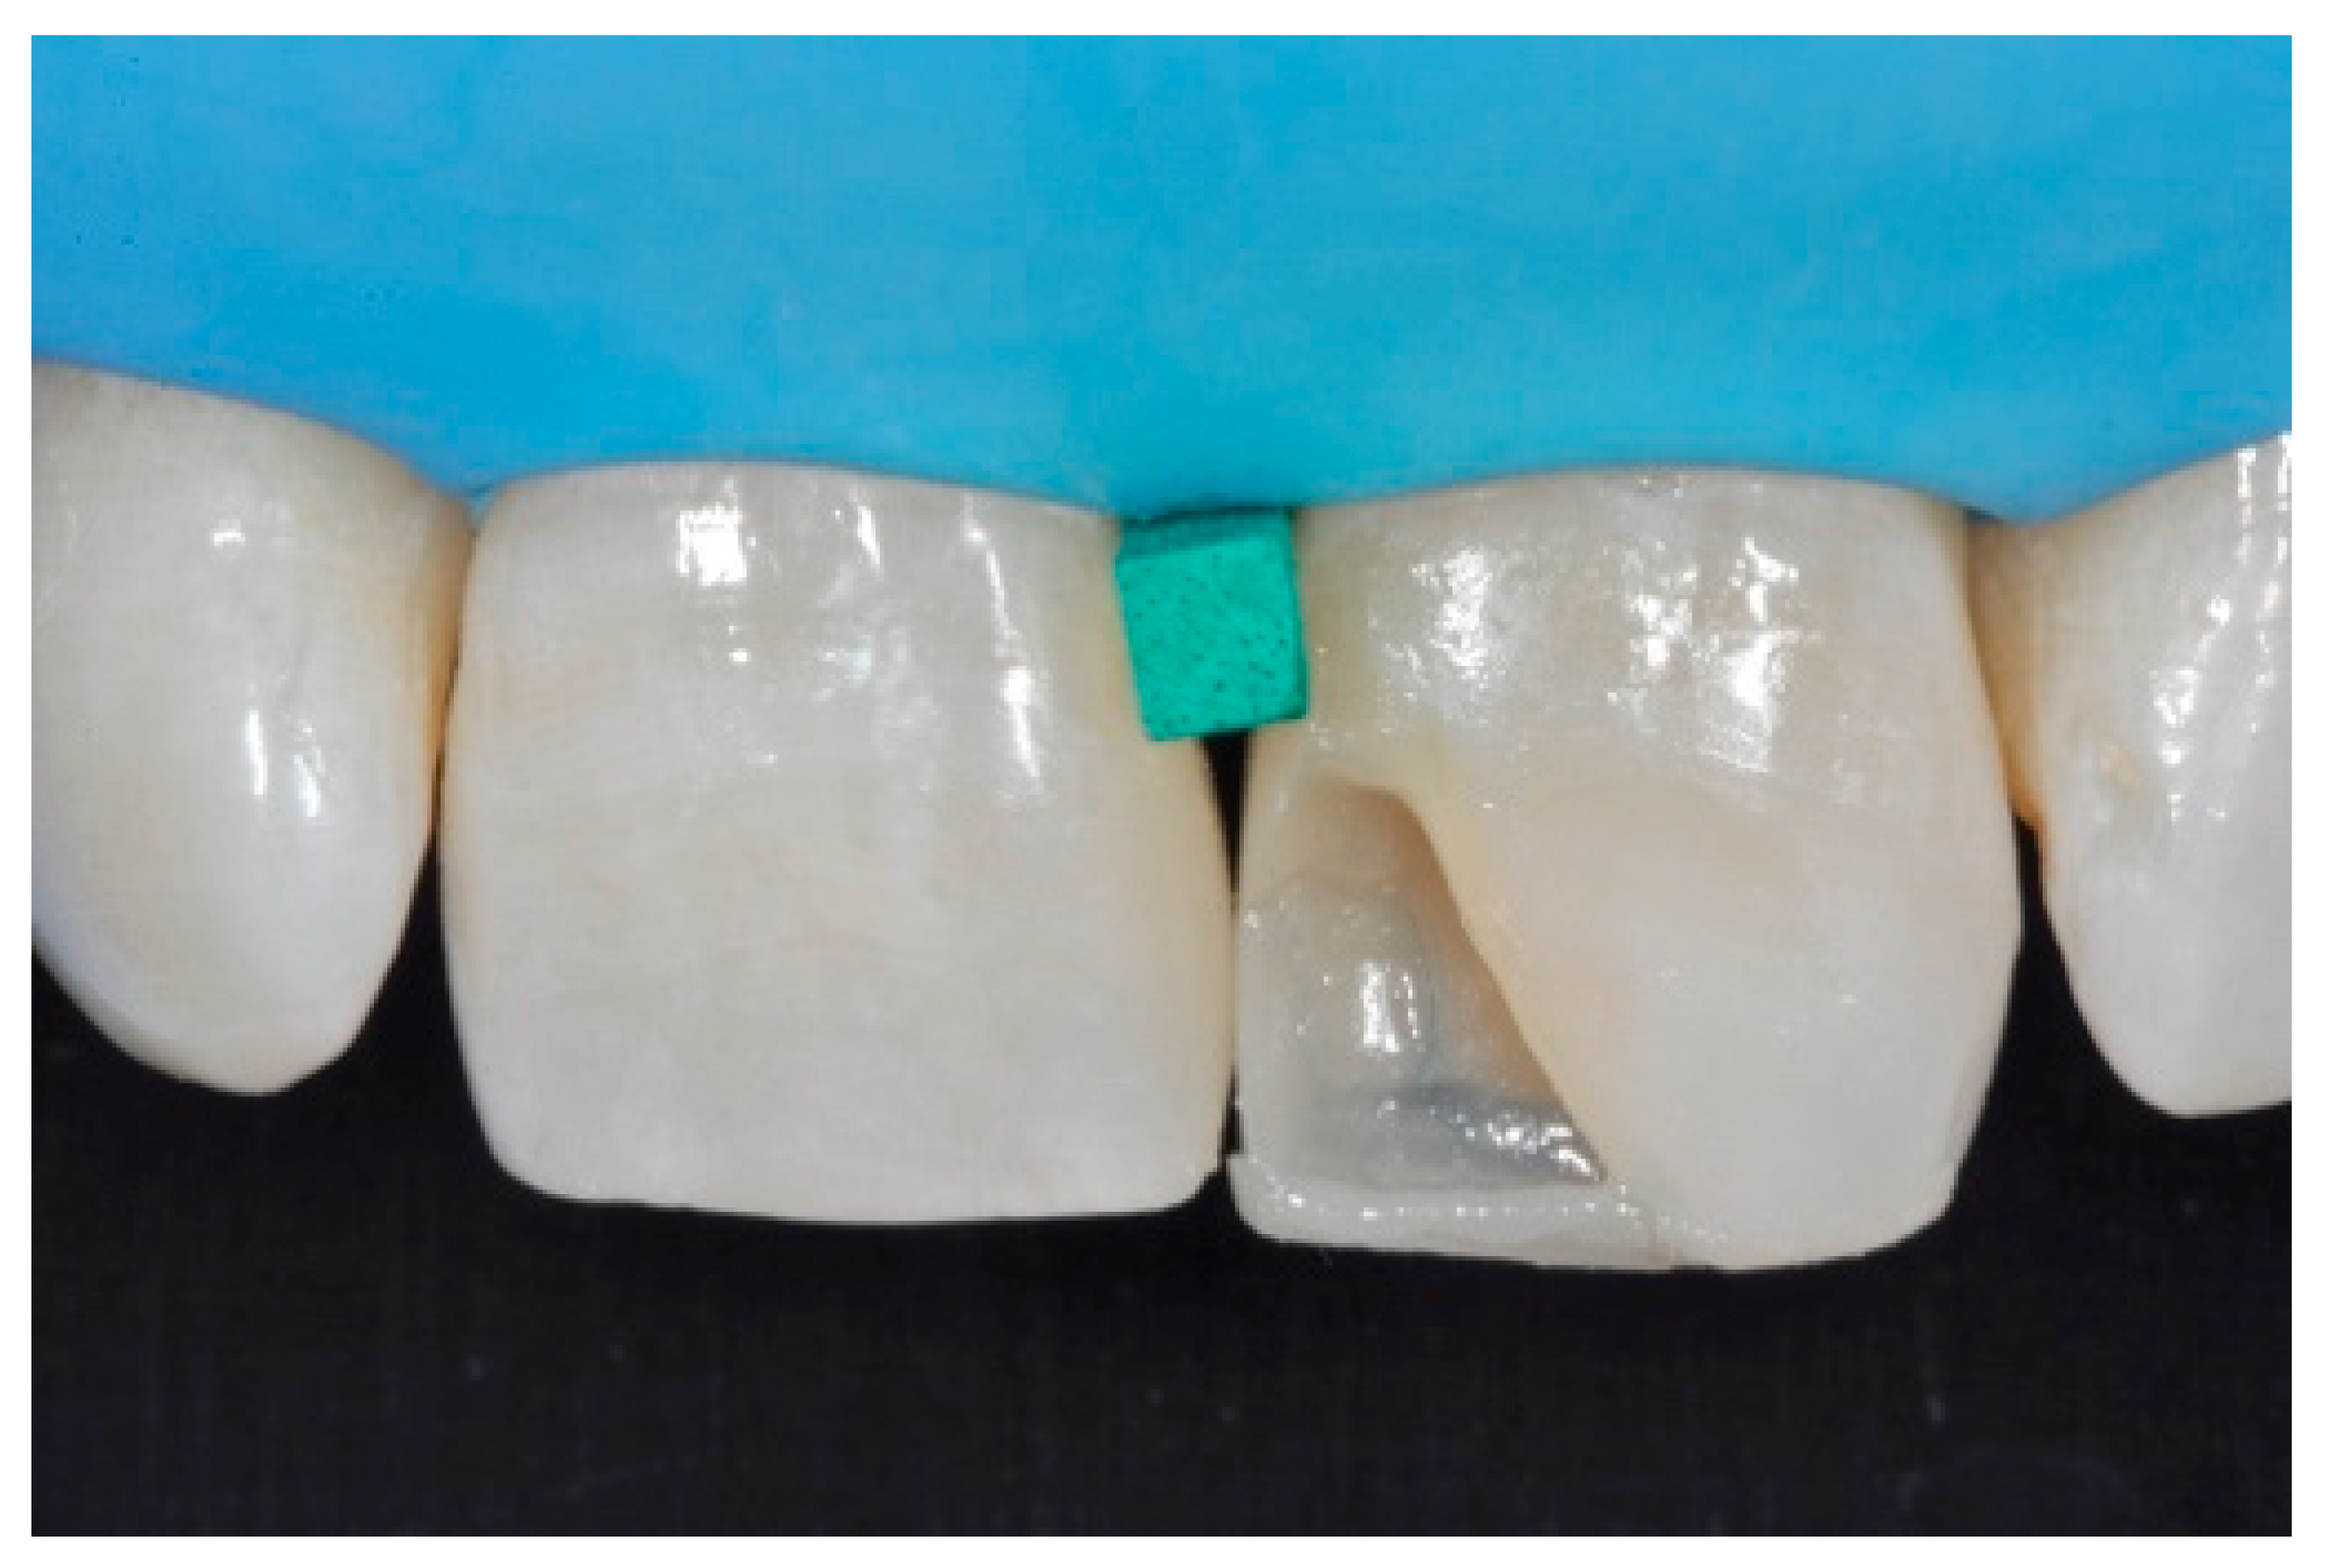

Before isolation with rubber dam, shade was selected using the button-try technique [14] applying composite samples on the teeth and light-curing them without performing previous adhesive procedures. The silicon index was checked in situ (Figure 4) and interferences were removed with scalpels. A two-step self-etch adhesive system (Clearfil SE Protect, Kuraray Noritake Dental, Tokyo, Japan) was applied following manufacturer’s instructions after selective enamel etching with a 38% phosphoric acid gel (Ultra-Etch, Ultradent Product, Inc., South Jordan, UT, USA). Light curing was applied with a visible light-curing unit with an intensity of 1000 mW/cm2 (Valo, Ultradent Products, South Jordan, UT, USA) for 20 s. A thin layer of composite enamel (Clearfil Majesty ES-2, A1E, Kuraray Noritake Dental, Tokyo, Japan) was applied on the silicone index in order to reproduce the palatal wall. The silicone index was then repositioned in the mouth and the palatal composite was adapted to the palatal margin of the preparation and light cured. Another increment was then applied to reproduce the incisal margin. The silicone index was then removed (Figure 5). In order to complete the frame, sectional matrices were applied vertically (Figure 6) and stabilized with wedges and interproximal drops of flowable cured to maintain the desired matrix position (Figure 6). Interproximal walls were then restored using the abovementioned composite enamel.

Figure 6.

Sectional matrices applied and stabilized with wedges and flowable drops. Reprinted from Restauri diretti nei settori anteriori, G. Paolone, S. Scolavino, © 2021, with permission from Quintessence Publishing Italy.